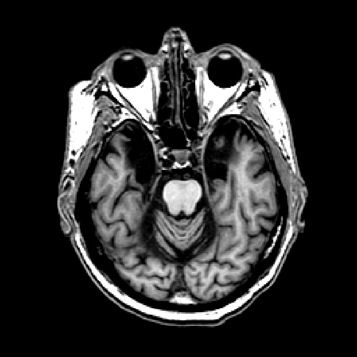

Der Hippocampus ist der größte Teil des Archicortex und ein Areal im Temporallappen. Er ist zudem ein wichtiger Teil des limbischen Systems. Funktional ist er an Gedächtnisprozessen, aber auch an räumlicher Orientierung beteiligt. Er umfasst das Subiculum, den Gyrus dentatus und das Ammonshorn mit seinen vier Feldern CA1-CA4.

Offenbar hatte Karl Lashley bei seinen Studien am falschen Ort gesucht. In seinen Rattenexperimenten hatte er stets Teile der Hirnrinde, also der äußersten Schicht des Gehirns entfernt. Dieses Hirnareal ist in der Entwicklungsgeschichte des Gehirns das jüngste, alle anderen hielt Lashley für zu primitiv. H.M. fehlte es aber nicht an Hirnrinde, Scoville hatte einen Teil des Mandelkerns, der Amygdala, entfernt und fast den gesamten Hippocampus. Diese Region an der Innenseite der Schläfenlappen war offenbar entscheidend für das Formen neuer Erinnerungen.

Eine weitere Merkwürdigkeit im Fall H.M: Ihm fehlte zwar das Langzeitgedächtnis, aber für ein paar Sekunden konnte er sich alles merken. Viele Versuche haben gezeigt, dass sein Kurzzeitgedächtnis in etwa so gut funktionierte wie das eines gesunden Menschen. Telefonnummern oder Wortlisten etwa konnte H.M. sich kurze Zeit merken, wurde er aber nach ein paar Minuten oder Stunden noch einmal gefragt, hatte er sie vergessen. „H.M. war der Paradefall, der gezeigt hat, dass der Hippocampus zentral ist für die Übertragung vom Kurzzeit– ins Langzeitgedächtnis“, sagt Markowitsch. Was auf lange Zeit abrufbar bleiben soll, das muss offenbar durch das Nadelöhr des Hippocampus. So haben Forscher mit bildgebenden Verfahren gezeigt, dass sich Menschen aus einer Liste von Wörtern an die am besten erinnern, bei deren Lernen der Hippocampus am stärksten aktiv war.